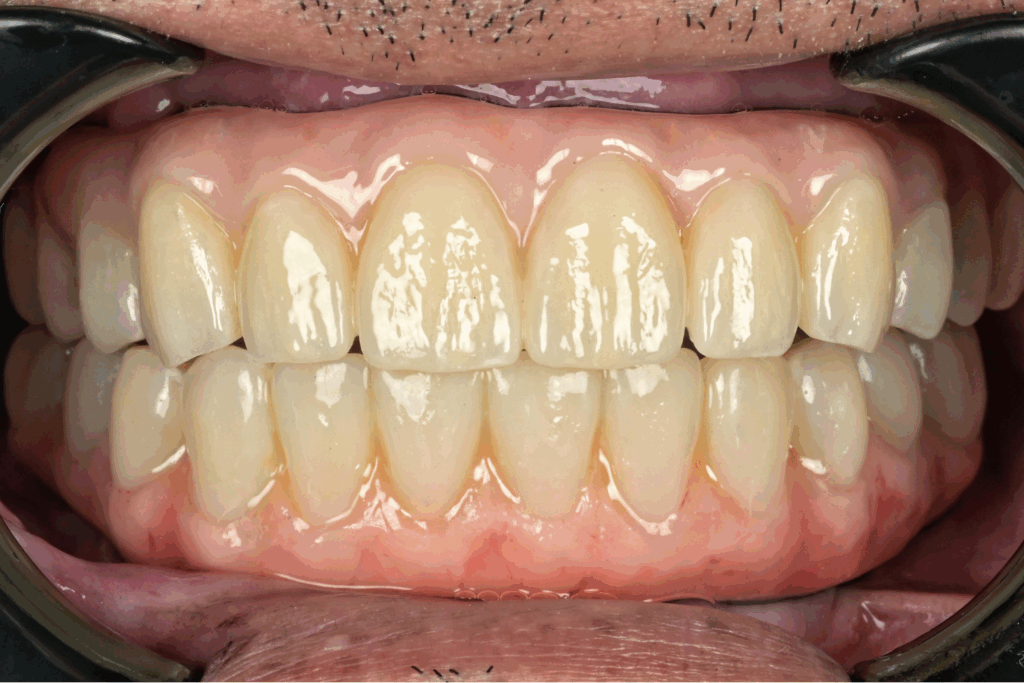

案例1. 上顎+下顎All on X

Before

After